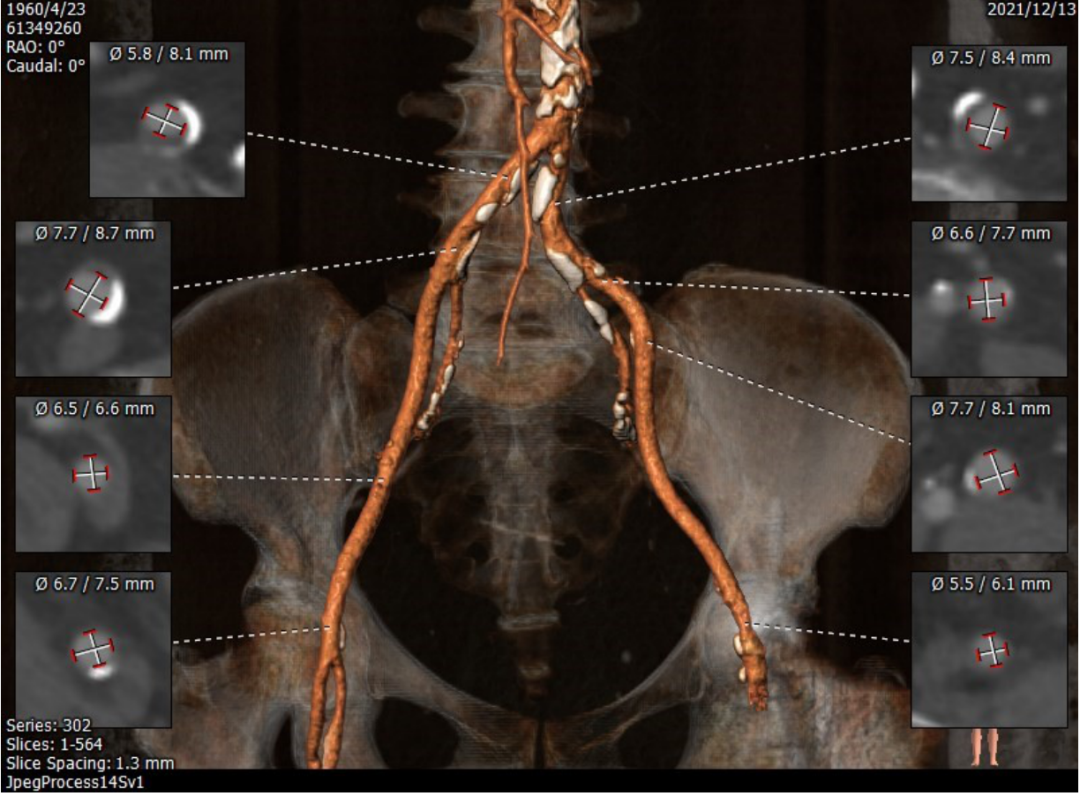

CT评估: